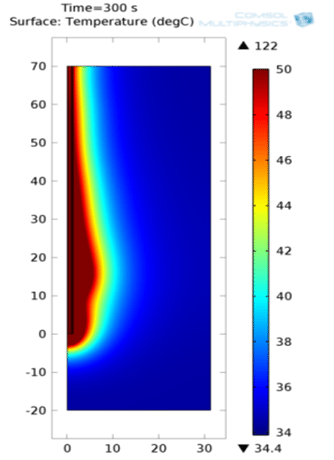

Computational Analysis of a Suitable Antenna and Optimized Frequency for Microwave Ablation of Breast Cancerous Tissue

The study aimed to simulate and analyze a suitable antenna operating at an optimized frequency for microwave ablation of breast...Read More